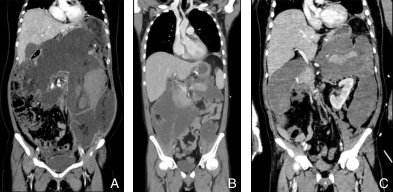

图1 INP影像学表现 A:坏死组织或液体积聚在胰周及左侧结肠旁沟;B:坏死组织或液体积聚在胰周及右侧结肠旁沟;C:坏死组织或液体积聚在胰周及双侧结肠旁沟Fig.1 Imaging features of INP A: Necrotic tissue or fluid accumulation in the peripancreatic region and left paracolic gutter; B: Accumulation in the peripancreatic region and right paracolic gutter; C: Accumulation in the peripancreatic region and bilateral paracolic gutter